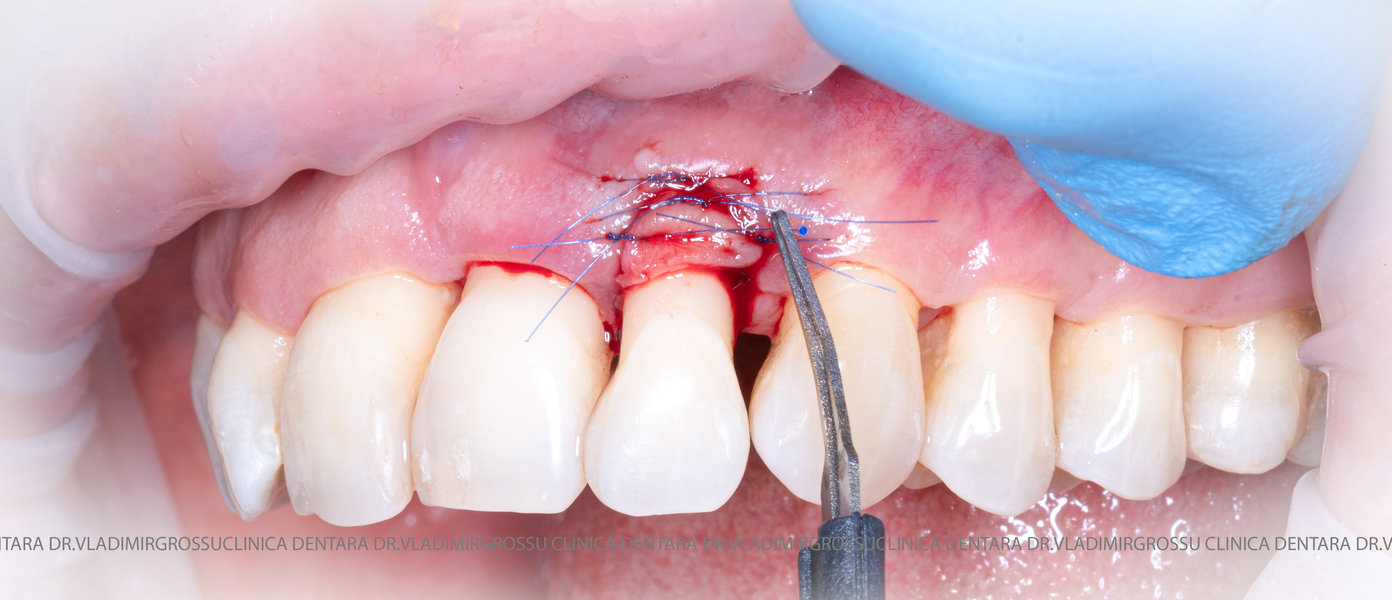

Aditia gingivală este o procedură chirurgicală ce corectează diverse probleme estetice și funcționale, cum ar fi recesiunea gingivală. În implantologia modernă, aditia de țesut moale este utilizată aproape în fiecare intervenție de inserție a implantului dentar pentru a asigura un aspect estetic natural și o bună integrare a implantului în cavitatea bucală.

Adiția osoasă are un rol crucial pentru poziționarea corectă și stabilă a implanturilor dentare. Clinica stomatologică Dr. Grossu din Chișinău promovează o abordare chirurgicală estetică și predictibilă, adaptată fiecărui caz în parte.